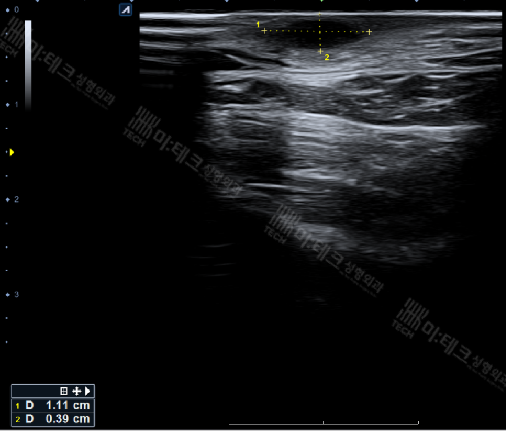

약 1.1cm 크기의 낭종이 확인되었고,

이미 단순 낭종을 넘어 피부와 피하조직에 염증이 퍼진 상태였기 때문에 단순 압출이나 약물 치료로는 호전이 어렵고,

외과적 절개와 배농이 필요하다고 판단했습니다.